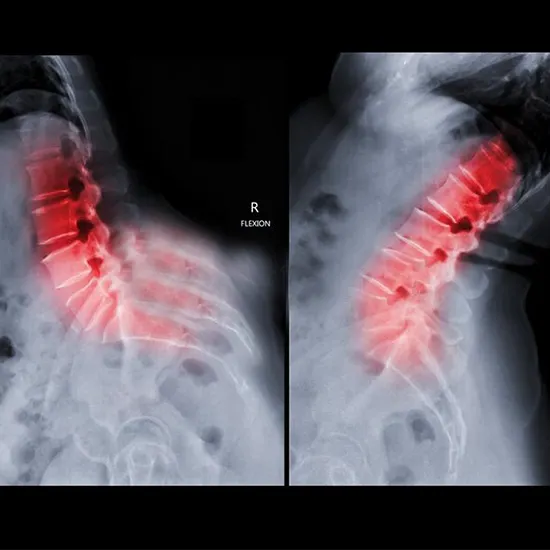

The lumbar spine flexion position is bending forward from the lower back. MRI LS (lumbosacral) spine flexion is an imaging procedure is used to see the changes in the spinal canal’s diameter, nerve compression, and vertebral instability.

• Spinal stenosis

• Compression of the nerve

• Dynamic changes in the spinal canal’s diameter

• vertebral instability

• Anterolisthesis (forward slippage of vertebrae)